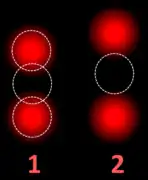

Fluorescence in situ hybridisation

FISH can be used to measure the number of copies of the gene which are present and is thought to be more reliable than immunohistochemistry.[45] It usually uses chromosome enumeration probe 17 (CEP17) to count the amount of chromosomes. Hence, the HER2/CEP17 ratio reflects any amplification of HER2 as compared to the number of chromosomes. The signals of 20 cells are usually counted.

This cell displays 2 signals of HER2 (red) and 3 signals of CEP17 (green)

Two signals that are closer to each other than the signal diameter count as one.

One of these signals is too faint, and is presumably debris.

Cells with only one type of signal are excluded from the count.

Overlapping cells are also excluded from the count.

A yellow signal counts as one red and one green (which are overlapping)